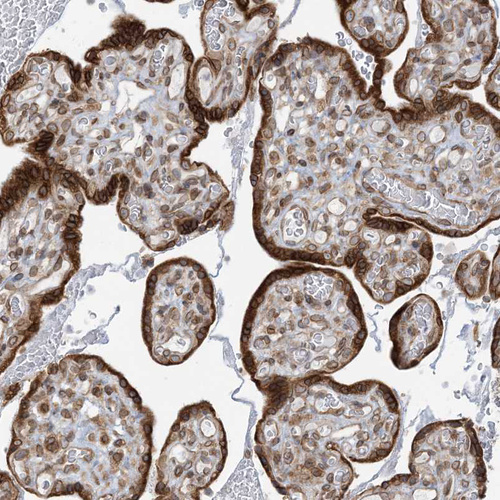

Immunohistochemical staining of human placenta shows strong cytoplasmic positivity in trophoblastic cells.